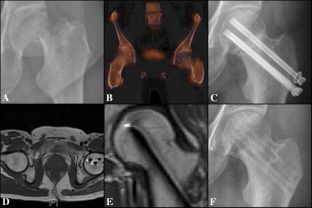

Fig. 2